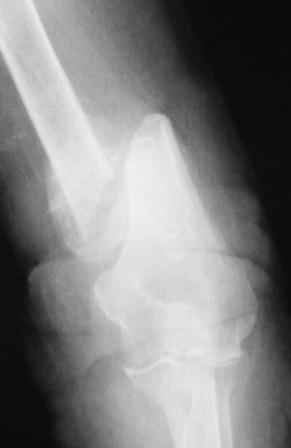

Уважаемые коллеги. Хочу продемонстрировать пример к недавней дискуссии о способности плечевой кости срастаться без операции.

Пациентка 87 лет, деменция, соматически сохранна. Конечность после травмы фиксирована в циркулярной бесподкладочной гипсовой повязке. Через месяц выявлена рана, образовавшаяся вседствие перфорации кожи острым концом дистального фрагмента. Далее - гипсовая лонгета и перевязки дома сиделкой. Через 2 месяца после травмы констатирована консолидация. По поводу концевого остеомиелита выполнена экономная резекция плечевой кости с ушиванием раны наглухо, заживление первичное.